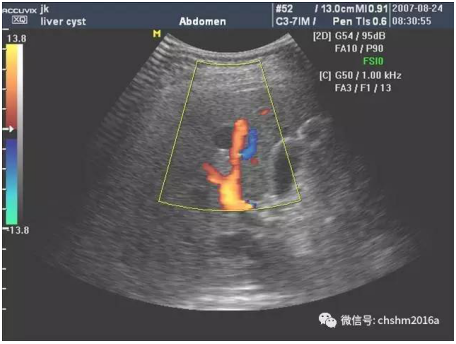

近日,我院綜合外科在同彩超室宋海霞主任的協(xié)作配合下共同完成一例在彩超引導(dǎo)下的肝囊腫穿刺、硬化術(shù)。手術(shù)患者為74歲女性,以頸痛伴眩暈入院,診斷為頸椎病,經(jīng)過對(duì)癥治療后患者病情好轉(zhuǎn),當(dāng)我科醫(yī)生在查看該患者的彩超檢查時(shí),卻意外地發(fā)現(xiàn)患者患有肝囊腫,并且符合穿刺、硬化治療的指征,在經(jīng)過與患者及家屬進(jìn)行有效的溝通后,手術(shù)于近日進(jìn)行。

超聲引導(dǎo)下肝囊腫硬化治療于70年代應(yīng)用于臨床,目前已經(jīng)成為肝囊腫的一種安全、有效的治療方法,具有全程可視、安全精準(zhǔn)、價(jià)格低廉、并發(fā)癥輕微、創(chuàng)傷小、恢復(fù)快等特點(diǎn),對(duì)肝囊腫的治愈率達(dá)90%以上。且對(duì)于復(fù)發(fā)的囊腫仍然可以再次進(jìn)行治療,因此在臨床上應(yīng)用越來(lái)越廣泛,如腎囊腫、多囊肝、多囊腎、卵巢囊腫、腘窩囊腫等。